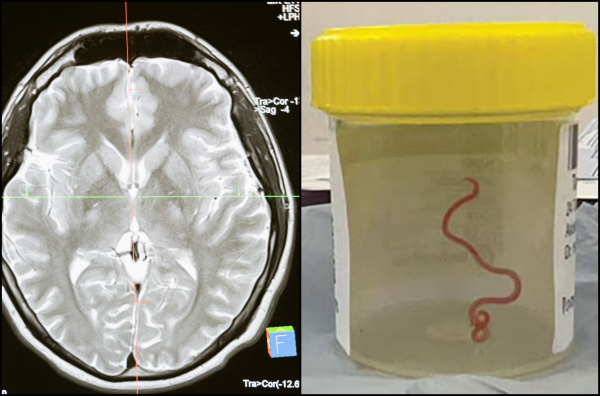

«Δεν θα πιστέψετε τι βρήκα στην ασθενή... κουνιέται»: Πώς βρέθηκε στον εγκέφαλο γυναίκας ζωντανό σκουλήκι

Είναι η πρώτη φορά παγκοσμίως που εντοπίζεται αυτό το παρασιτικό σκουλήκι σε άνθρωπο!